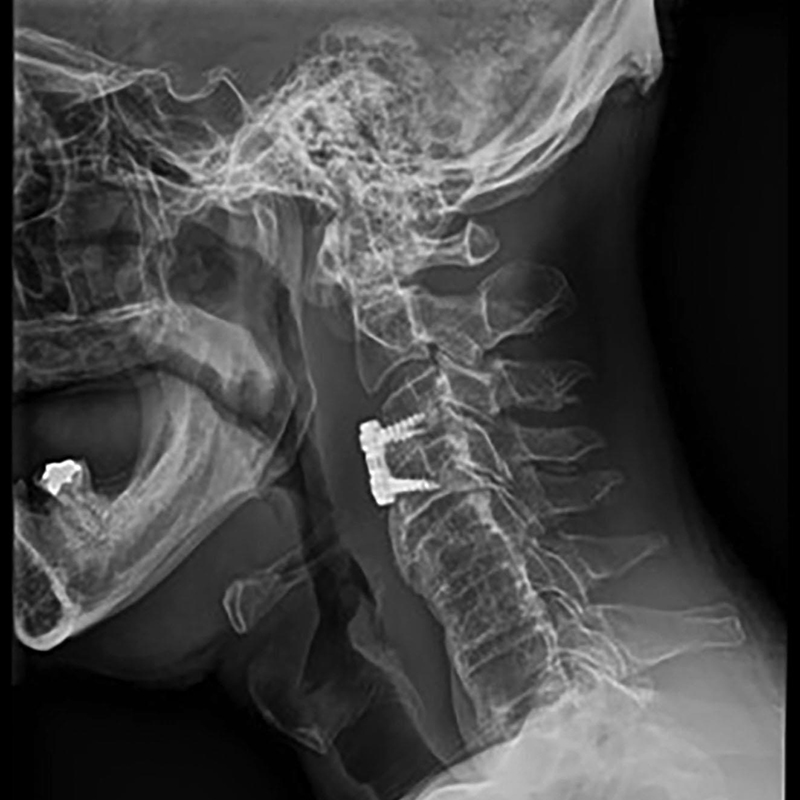

Ca lâm sàng và câu hỏi Bệnh nhân nam, 60 tuổi đi khám vì đau cổ tiến triển từ vài tháng nay, tê rần cánh tay phải, và bàn tay phải trở nên vụng về. Ông cho biết ngày càng mất thăng bằng trong đi lại, mặc dù vẫn còn khả năng làm công việc của một người quản gia. Dấu hiệu sinh tồn không có gì đặc biệt. Các […]